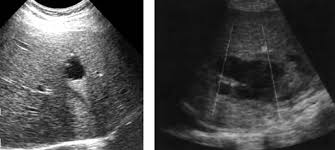

Ecografía abdominal en urgencias, sugiere masa que depende de cabeza de páncreas versus masa lobulada en zona del hígado, no líquido libre.

Mujer 74 años con antecedentes de adenocarcinoma endometrial hace aproximadamente 20 años (histerectomizada) Acude al servicio de urgencias por dolor abdominal de tipo epigastralgia que empeora con las comidas,  acompañado de  síndrome constitucional de tres semanas de evolución (pérdida de apetito y pérdida de peso, no cuantificada, de 3 semanas de  evolución. Alterna estreñimiento y diarrea. No heces de característica melénicas. No fiebre. No clínica infecciosa por aparatos  o sistemas. A la exploración física abdomen con  ruidos hidroaéreos normales, blando, depresible, no irritación peritoneal, doloroso a la palpación profunda en epigastrio e hipocondrio derecho, se palpa masa a nivel de hipocondrio derecho  y epigastrio, de unos 3 - 4 cm.